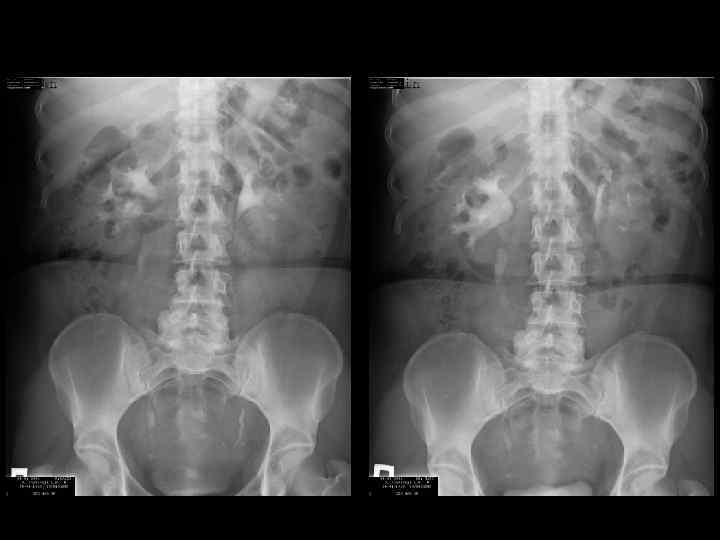

норма